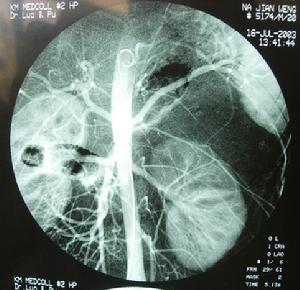

4.數字減影血管造影 可了解主要血管的受侵及腫瘤的主要供血動脈,有助於術中處理腫瘤的主要血管在行數字減影血管造影術的同時,如果發現腫瘤有主要滋養血管可同時進行介入治療和血管栓塞,使腫瘤壞死縮小,便於再手術。

由於腹膜後復發性腫瘤局部解剖關係發生改變、腫瘤大、位置深、操作空間小、容易傷及腹膜後大血管,再手術時出血量較大。術前對出血量要有充分估計並有足夠的備血量。才能保證手術的完成。如有條件,術前應行數字減影血管造影術檢查,找到主要供血動脈行栓塞治療可減少術中出血,但腫瘤惡性程度高血供豐富者,往往有多處供血動脈,栓塞止血效果往往不夠滿意。